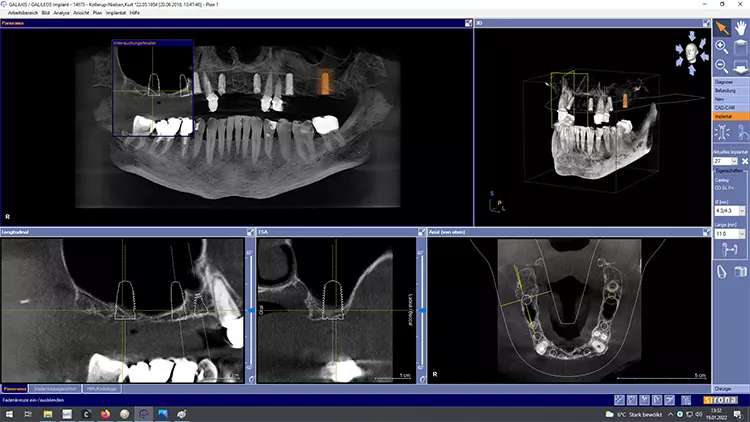

Die Implantatmaße und -positionen sowie der Umfang der Sinusbodenelevation wurden dabei in Sinne eines „backward planning“ anhand von DVT-Aufnahmen bestimmt. Zahn 13 sollte noch vorübergehend erhalten bleiben, um zusammen mit den bleibenden Zähnen 23 und dem entsprechend kariesbehandelten Zahn 24 bis zur Fertigstellung der definitiven Restauration der alten Teleskopprothese als Interimsersatz Halt zu geben. Als definitive Versorgung wurden drei VMK-Brücken auf NEM-Gerüsten vorgesehen. Damit sollte auch die natürliche Bezahnung im Unterkiefer von 37 bis 47 abgestützt werden.

Nach einer – aufgrund eines Campingurlaubs von sechs auf acht Monaten – verlängerten Heilphase konnte der Patient implantiert werden. In der Röntgenkontrollaufnahme zeigten sich stabile knöcherne Strukturen in den augmentierten Bereichen des Sinus. Die Insertionen erfolgte gemäß Protokoll frei Hand auf Grundlage der DVT-Aufnahme und orientiert an der alten Teleskopprothese.